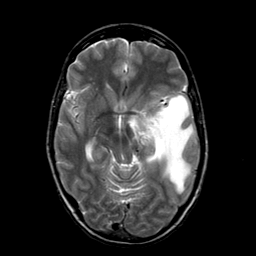

Metastatic bronchogenic carcinoma, overlay -- Slice #9

[Home][Help][Clinical] Slice 9